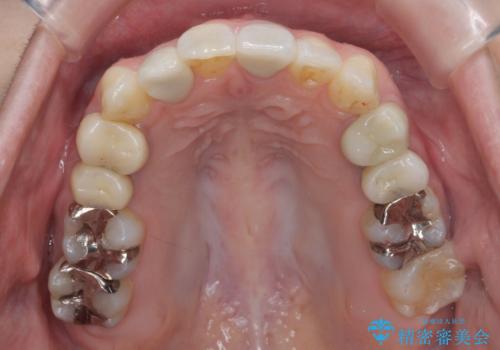

前歯のがたつきを主訴に来院。

ワイヤー矯正の古典的な治療方針である、4本抜歯して全体ワイヤーでも構わないとのことでした。

4本抜歯すると口元が下がりすぎてしまうため、下の前歯のみ1本抜歯および上顎の前歯が大きいため少し削らせてもらう提案をしました。

右上2番をしっかり並べるにはワイヤー矯正を上顎部分的に用いて、最後全体マウスピース治療を行いました。

上顎前歯は神経がない歯で色も変わってきていたためセラミックでかぶせています。